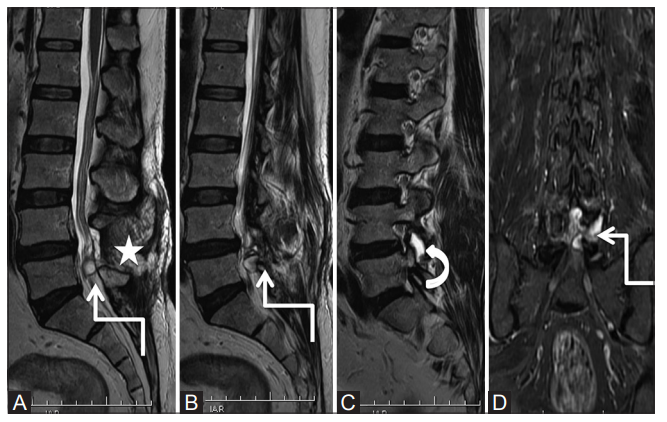

Abcès Epidural

- Sur spondylodiscite/Ostéomyélite ++

- T1: iso à hypo à au cordon

- T2: Hyper

- DWI: restriction

- T1 C+: phlegmon réhausse, abcès réhausse en périphérie